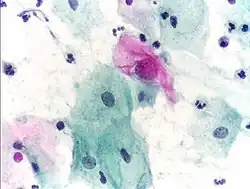

- Cytopathology – the examination of loose cells spread and stained on glass slides using cytology techniques

Cytopathology is a sub-discipline of anatomical pathology concerned with the microscopic examination of whole, individual cells obtained from exfoliation or fine-needle aspirates. Cytopathologists are trained to perform fine-needle aspirates of superficially located organs, masses, or cysts and are often able to render an immediate diagnosis in the presence of the patient and consulting physician. In the case of screening tests such as the Papanicolaou smear, non-physician cytotechnologists are often employed to perform initial reviews, with only positive or uncertain cases examined by the pathologist. Cytopathology is a board-certifiable subspecialty in the U.S.